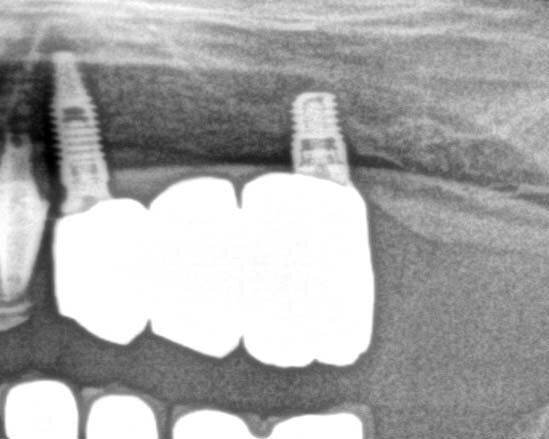

Dopo tre settimane è stata presa l’impronta finale con la tecnica del cucchiaio aperto, eseguita la registrazione occlusale e dopo tre settimane è stato consegnato un ponte in zirconio fresato ritenuto da viti e con successivo controllo radiografico (Figg. 8, 9).

Ad un anno di distanza dalla consegna è stato eseguito un controllo radiografico (Fig. 10). Il dettaglio ingrandito della radiografia periapicale evidenziava una maturazione dell’osso attorno all’apice dell’impianto all’interno del seno mascellare. Clinicamente il tessuto gengivale appariva sano e senza alterazioni.